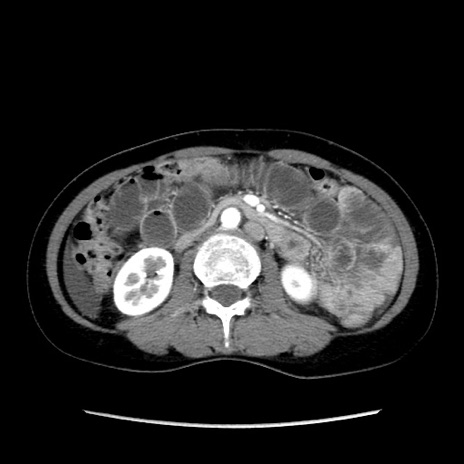

症例32(横断像)

【症例】40歳代 女性

【主訴】上腹部痛、嘔気・嘔吐

【現病歴】約9時間前頃から急に上腹部痛、嘔気、嘔吐が出現。改善しないため救急要請。

【既往歴】子宮頚癌(広汎子宮全摘術、放射線療法)、腸閉塞

【身体所見】腹部:平坦、軟、腸雑音亢進、上腹部を中心に腹部全体に圧痛あり。

【データ】WBC 8400、CRP 0.03